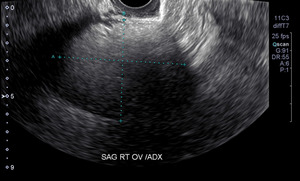

We referred our patient to a gynecologist at the recommendation of the chiropractic radiologist that read the films. To confirm the suspected diagnosis, the gynecologist referred the patient for ultrasound imaging (Fig 2). The patient then underwent an oophorectomy. Although the risk is relatively small (0.8%-5.5% of cases), there does exist a chance for malignant degeneration.1,15–17 She reports infrequent, mild low back pain post-surgery.